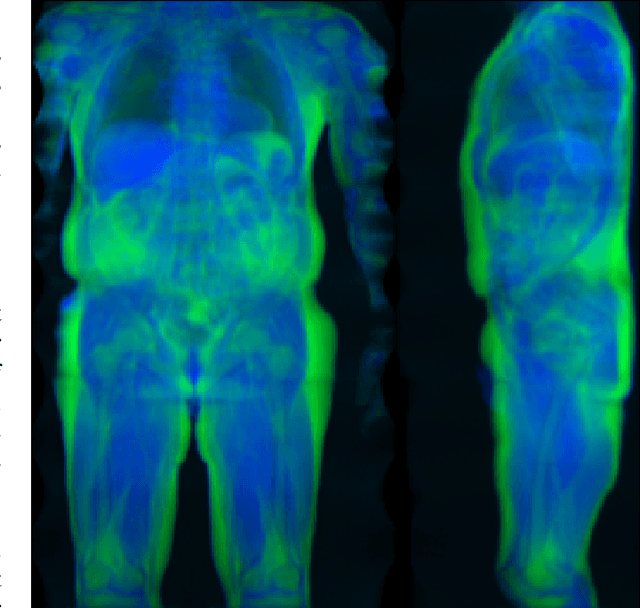

Abstract:Purpose: To perform and evaluate water and fat signal separation of whole-body gradient echo scans using convolutional neural networks. Methods: Whole-body gradient echo scans of 240 subjects, each consisting of five bipolar echoes, were used. Reference fat fraction maps were created using a conventional method. Convolutional neural networks, more specifically 2D U-nets, were trained using 5-fold cross-validation with one or several echoes as input, using the squared difference between the output and the reference fat fraction maps as the loss function. The outputs of the networks were assessed by the loss function, measured liver fat fractions, and visually. Training was performed using a GPU. Inference was performed both using the GPU as well as a CPU. Results: The final loss of the validation data decreased when using more echoes as input, and the loss curves indicated convergence. The liver fat fractions could be estimated using only one echo, but results were improved by use of more echoes. Visual assessment found the quality of the outputs of the networks to be similar to the reference even when using only one echo, with slight improvements when using more echoes. Training a network took at most 28.6 h. Inference time of a whole-body scan took at most 3.7 s using the GPU and 5.8 min using the CPU. Conclusion: It is possible to perform water and fat signal separation of whole-body gradient echo scans using convolutional neural networks. Separation was possible using only one echo, although using more echoes improved the results.